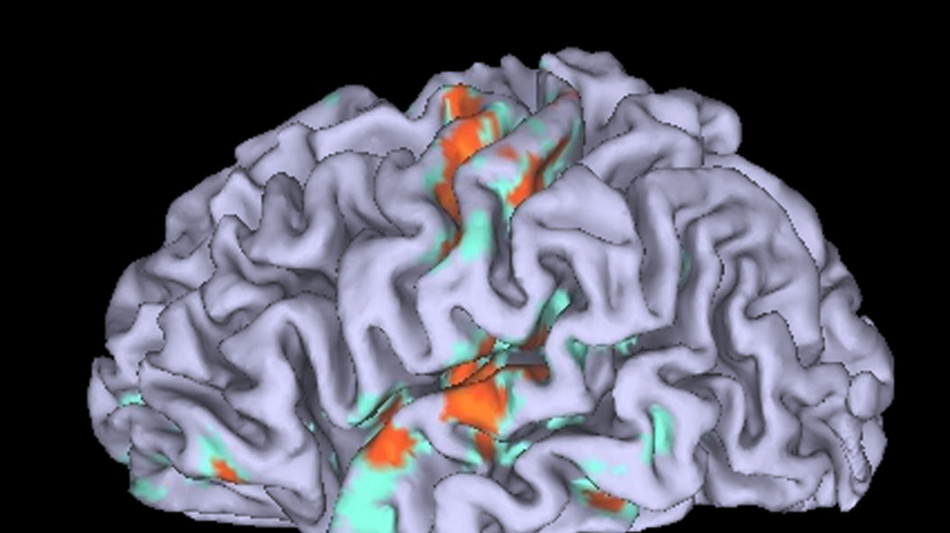

L'immaginazione non è la mera riproduzione nel cervello di determinate percezioni sensoriali, bensì un'attività più complessa che coinvolge funzioni cognitive di livello superiore che ci aiutano a imparare, pianificare ed evitare pericoli senza doverne necessariamente fare esperienza diretta. Lo dimostra lo studio pubblicato sulla rivista Neuron dai ricercatori della Nothwestern University negli Stati Uniti. "Quando si chiede a qualcuno di immaginare il suono di una festa di compleanno per bambini, non si limita a sentirlo, ma visualizza automaticamente anche la scena", osserva il neurologo Rodrigo Braga, coordinatore dello studio. "È logico che l'immaginazione operi in questo spazio olistico di livello superiore, dato che la usiamo per pianificare, comprendere e ipotizzare". I ricercatori sono giunti a questa conclusione dopo aver sottoposto otto volontari alla risonanza magnetica funzionale per valutare l'attività del loro del cervello mentre immaginavano diversi scenari. Per ciascun partecipante sono state mappate le reti sensoriali e associative nel cervello, confrontando poi l'attività cerebrale durante l'immaginazione con l'attività durante la percezione effettiva. Si è così scoperto che l'attività cerebrale correlata all'immaginazione e quella legata alla percezione si sovrappongono nelle aree associative di livello superiore, non nelle aree sensoriali primarie. ". Quando le persone immaginano scene complesse o un dialogo interiore, la maggiore sovrapposizione con la percezione si verifica nelle fasi successive, dove la sensazione è già stata trasformata in significato", sottolinea Braga. "Queste aree associative sono particolarmente interessanti perché sono notevolmente più estese nel cervello umano rispetto ai nostri antenati evolutivi più prossimi; inoltre permettono agli esseri umani di fare cose in cui siamo particolarmente avanzati, come comunicare usando il linguaggio". I partecipanti allo studio hanno riferito di percepire immagini mentali molto più vivide durante l'immaginazione di scene e sensazioni uditive altrettanto realistiche quando pensavano a discorsi o parole.